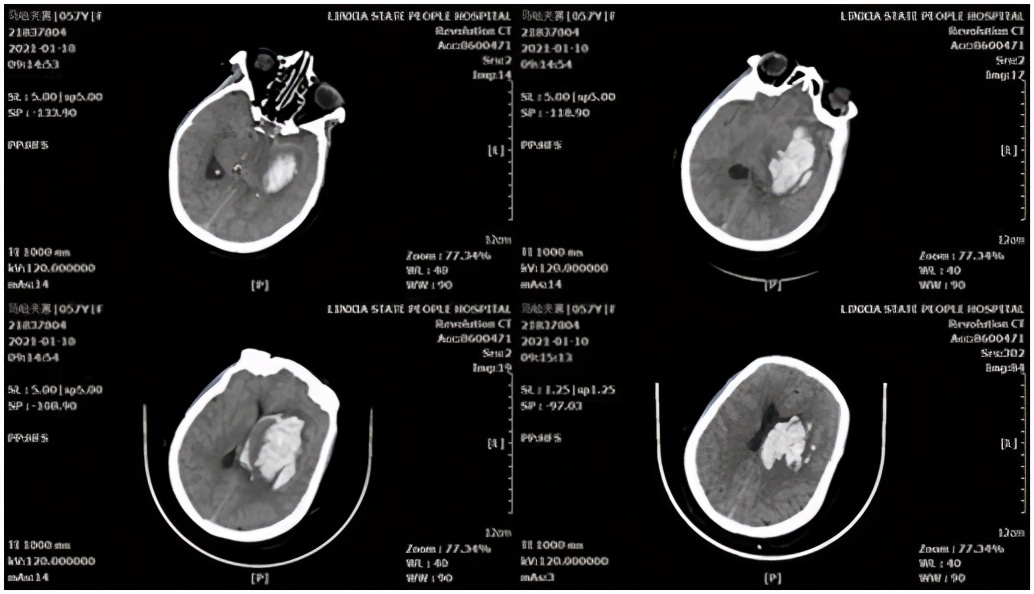

基底节区脑血肿病例,患者女性,58岁。主因“突发意识障碍、呕吐伴右侧肢体无力4小时”,急诊以“高血压脑出血”收入院,头颅CT示显示:左侧基底节区脑出血破入脑室。

术前头颅CT

术中采用额中回入路,并用血肿-脑脊液置换技术,最终清除基底节区、脑室内全部血肿,术后血肿腔不放置引流管,取得了良好效果。

术后头颅CT